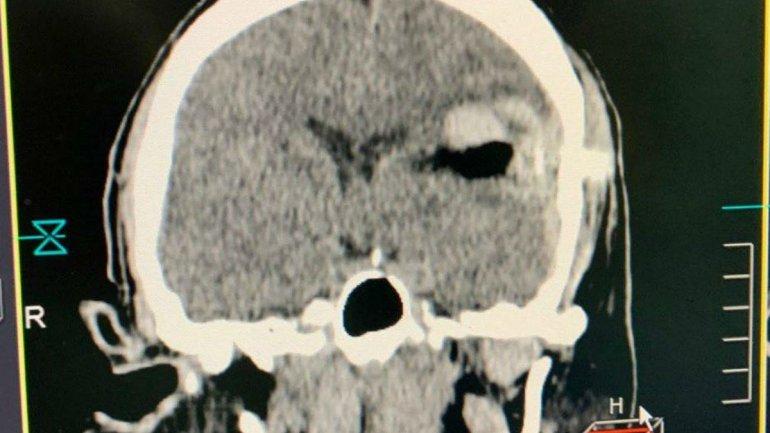

‘Он ранен возле Авдеевки. Тяжелое проникающее черепно-мозговое ранение, внутримозговое кровоизлияние лобно-височно-теменной области. Металлический осколок прорубил кости черепа, прошёл сквозь мозг’, – написал Сергей Рыженко.